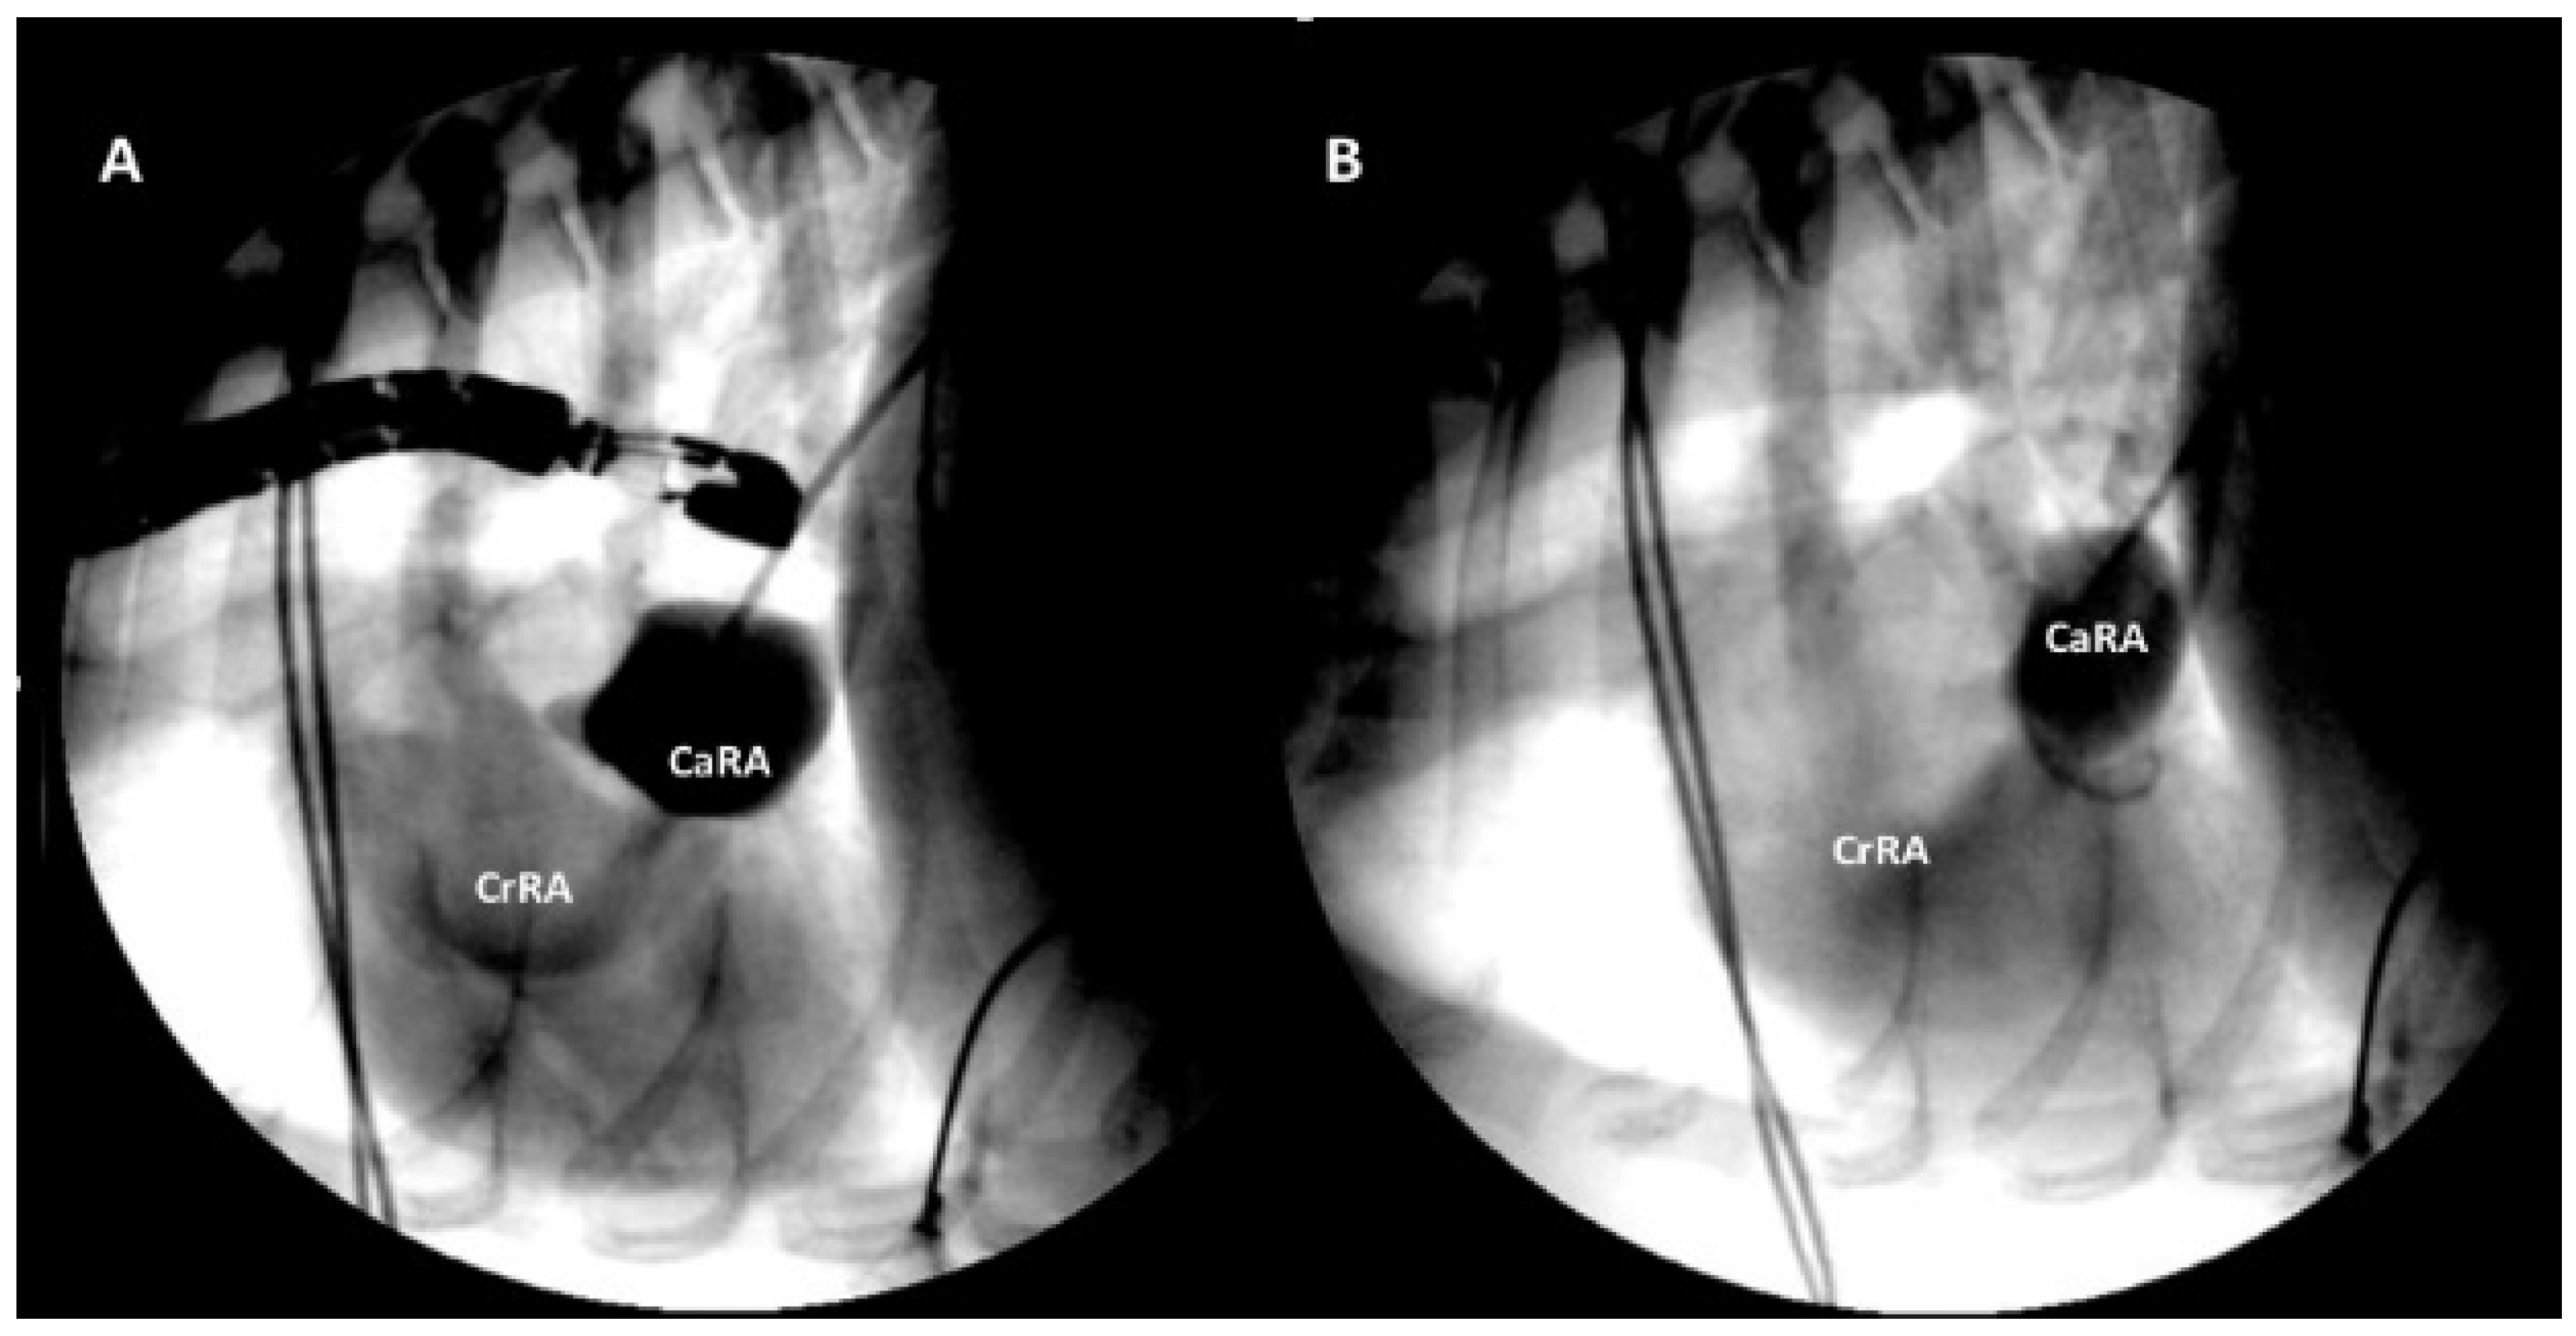

2.1. Case 1

2.2. Case 2